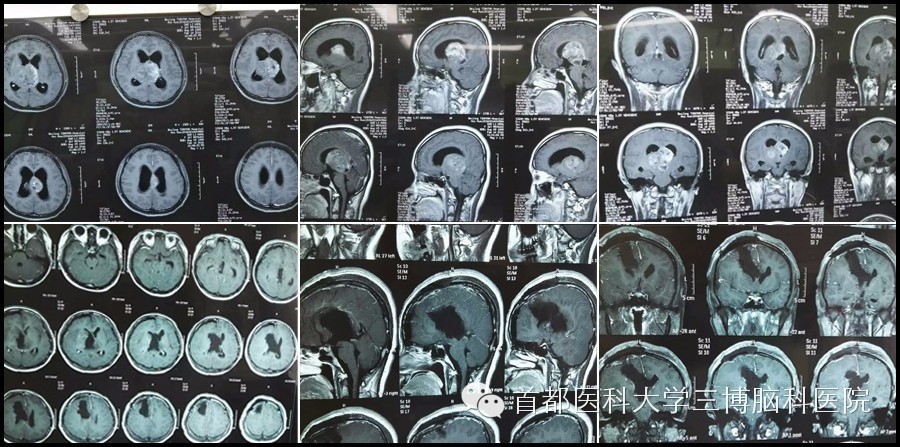

这位病友是我师兄介绍来的,为胶质母细胞瘤。术前师兄鼓励我:长祥啊!你放开做,我和病友家属已经充分沟通过,出现任何不测,家里都能接受。但是作为医生,只要有一丝希望都要做百分努力,不希望发生任何不测。

术前病友家属真的很理解,对我们也非常信任,这确实增加了我们的信心。手术过程很顺利,术后病友也很快清醒,并能下床活动。但术后一周病友发烧,多少还是给我们带来了一定的压力。还好,经过两周多的努力,体温彻底恢复正常。

再次和孩子的父母沟通下一步的治疗,父母的态度很积极也很理性,表示能恢复成这样已经非常满意。孩子看起来压力也不大,看到她每天满脸轻松的在走廊活动(病理是胶母,但没告诉她),我们也确有一种成就感,祝愿下一步的治疗也能有一个好结果,以实现她的大学梦!